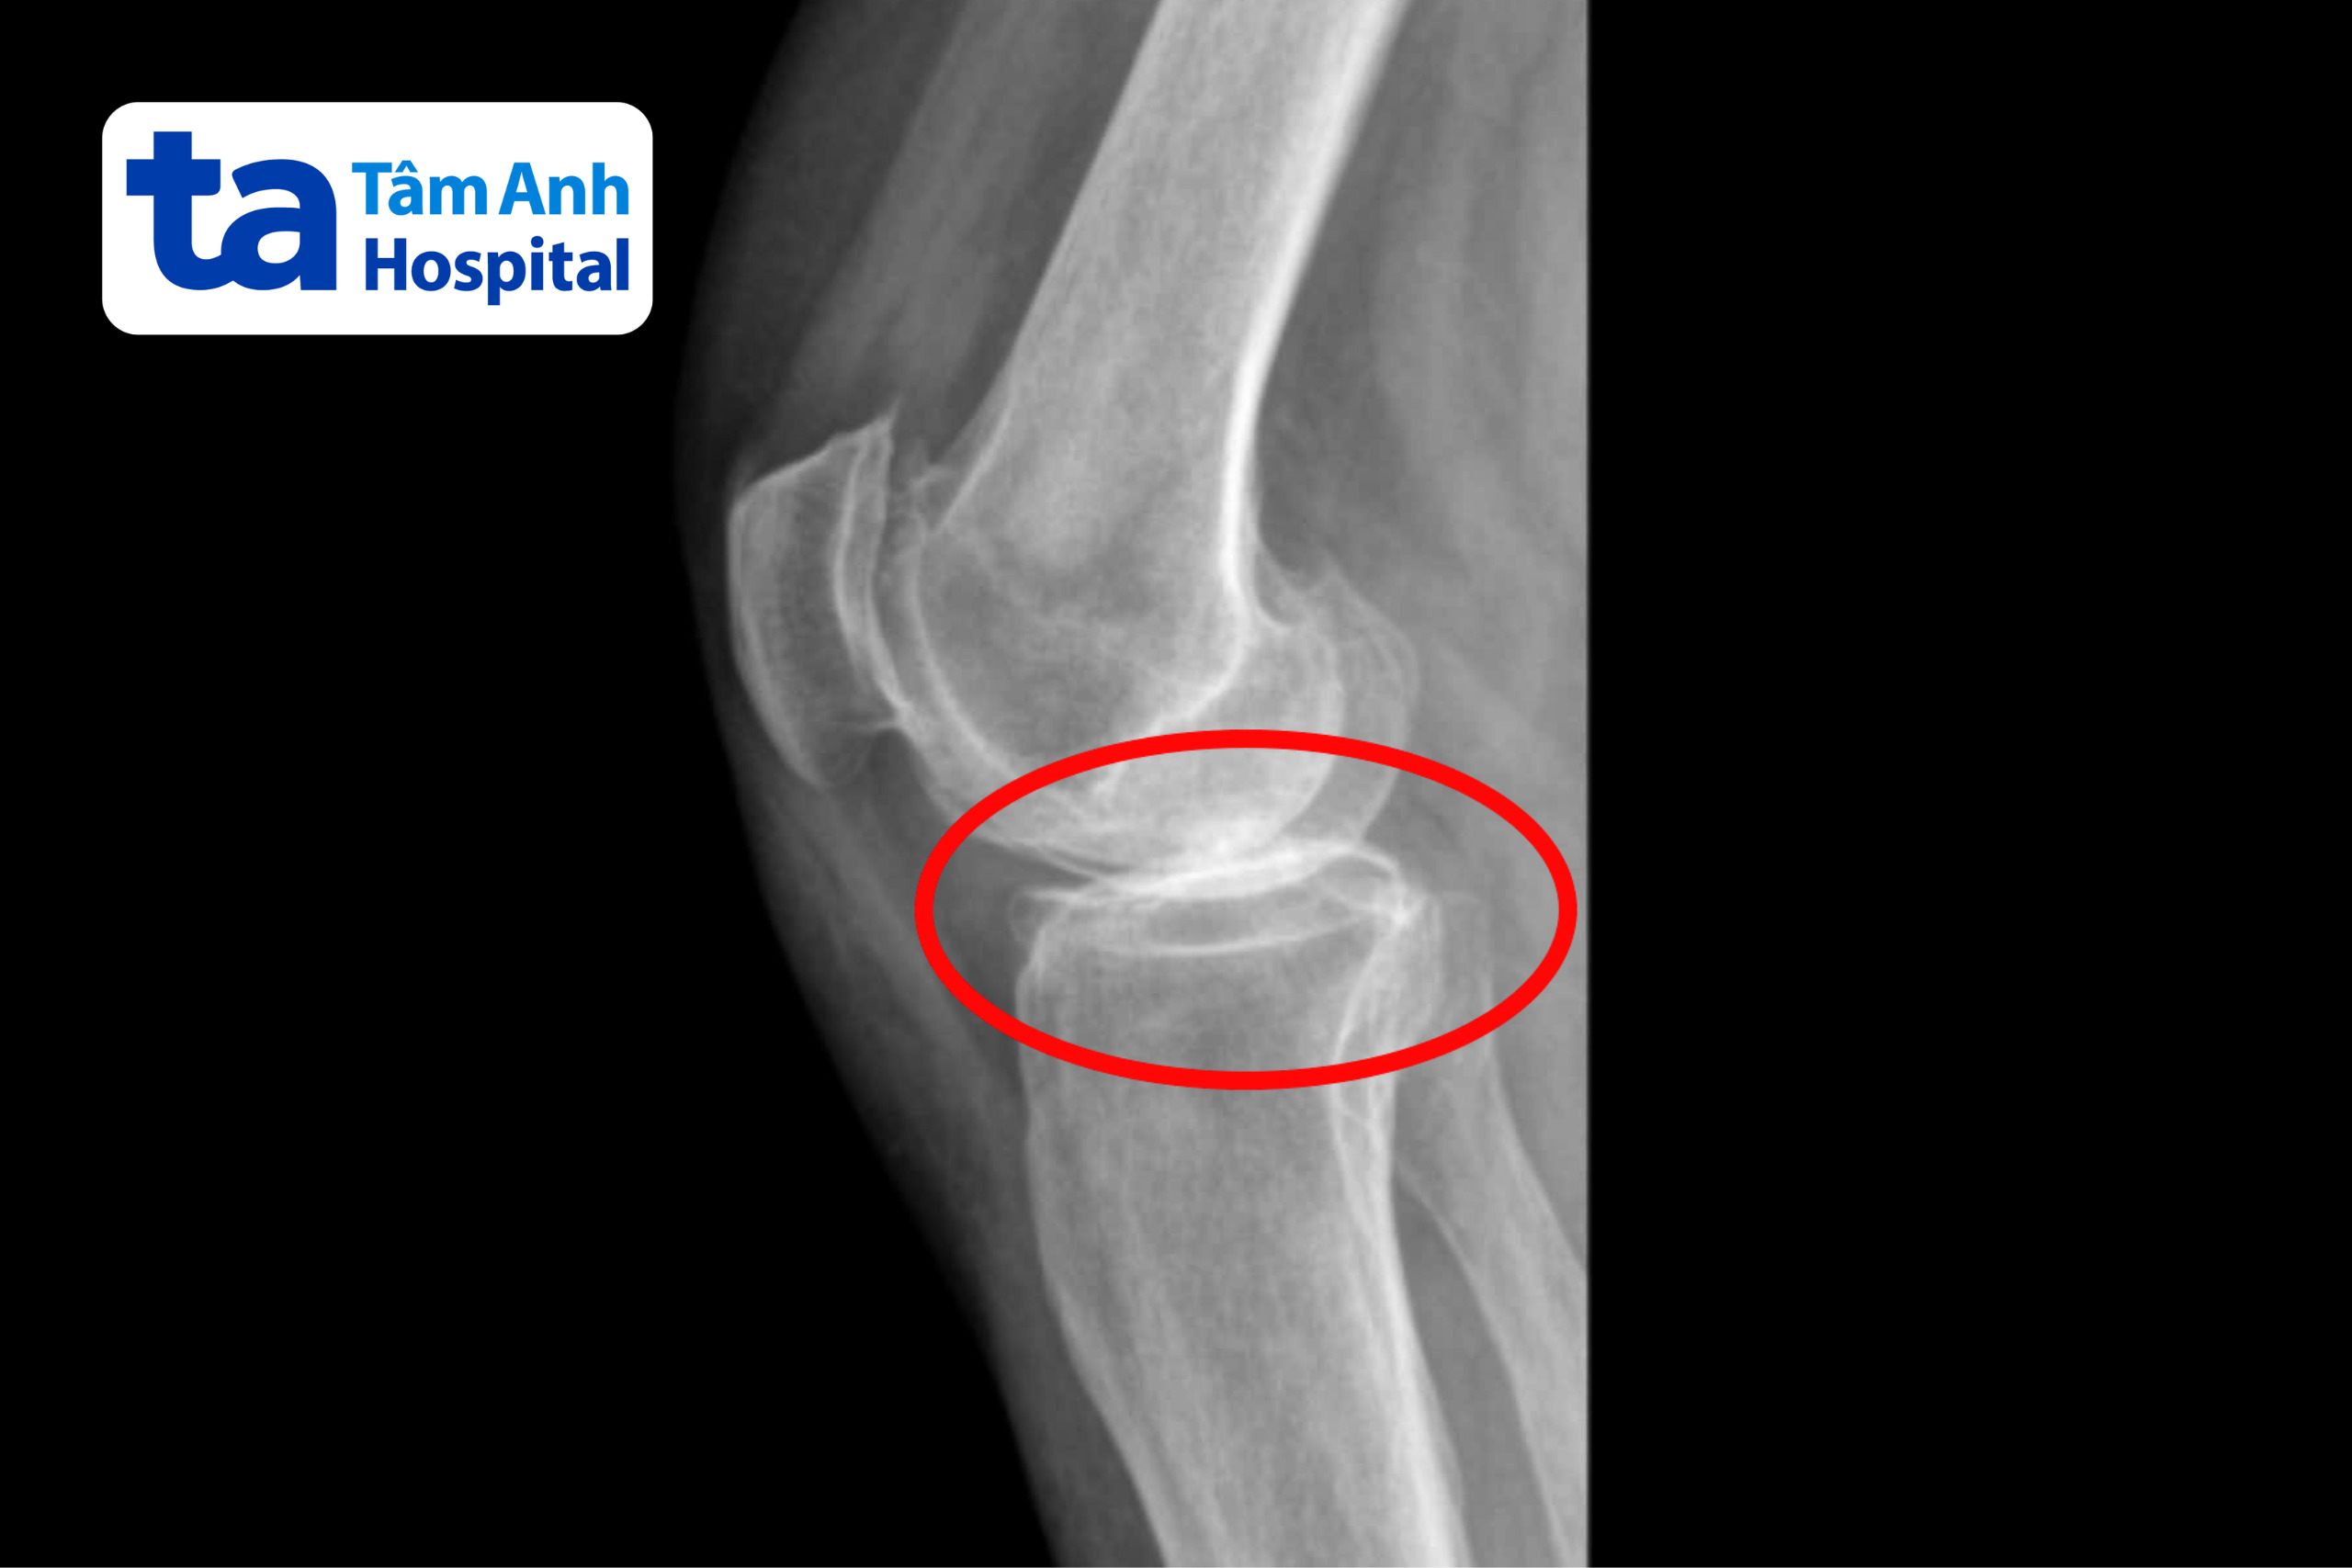

Bà Victoria (quốc tịch Mỹ) được chẩn đoán thoái hóa khớp gối mạn tính giai đoạn 4. Cơn đau ngày càng nặng hơn, bà không thể lên xuống cầu thang, không thể đi đoạn đường dài quá vài chục mét và rất dễ té ngã.

ThS.BS.CKI Đặng Khoa Học, Trưởng khoa Chấn thương Chỉnh hình Tổng quát, Bệnh viện Đa khoa Tâm Anh TP HCM, cho biết, thoái hóa khớp gối mạn tính giai đoạn 4 như bà Victoria là giai đoạn nghiêm trọng nhất của bệnh, sụn khớp gần như không còn nguyên vẹn, các đầu xương chạm trực tiếp vào nhau và dịch viêm do thoái hóa gây đau và cứng khớp. Người bệnh buộc phải thay đổi dáng đi để giảm đau nhưng vô tình làm tăng áp lực lên cột sống thắt lưng, gây đau và chèn ép thần kinh tọa. Hậu quả là cơ đùi hai bên yếu đi, trong thời gian dài không đi lại được nhiều nên cơ tứ đầu đùi của bà Victoria bắt đầu teo lại.